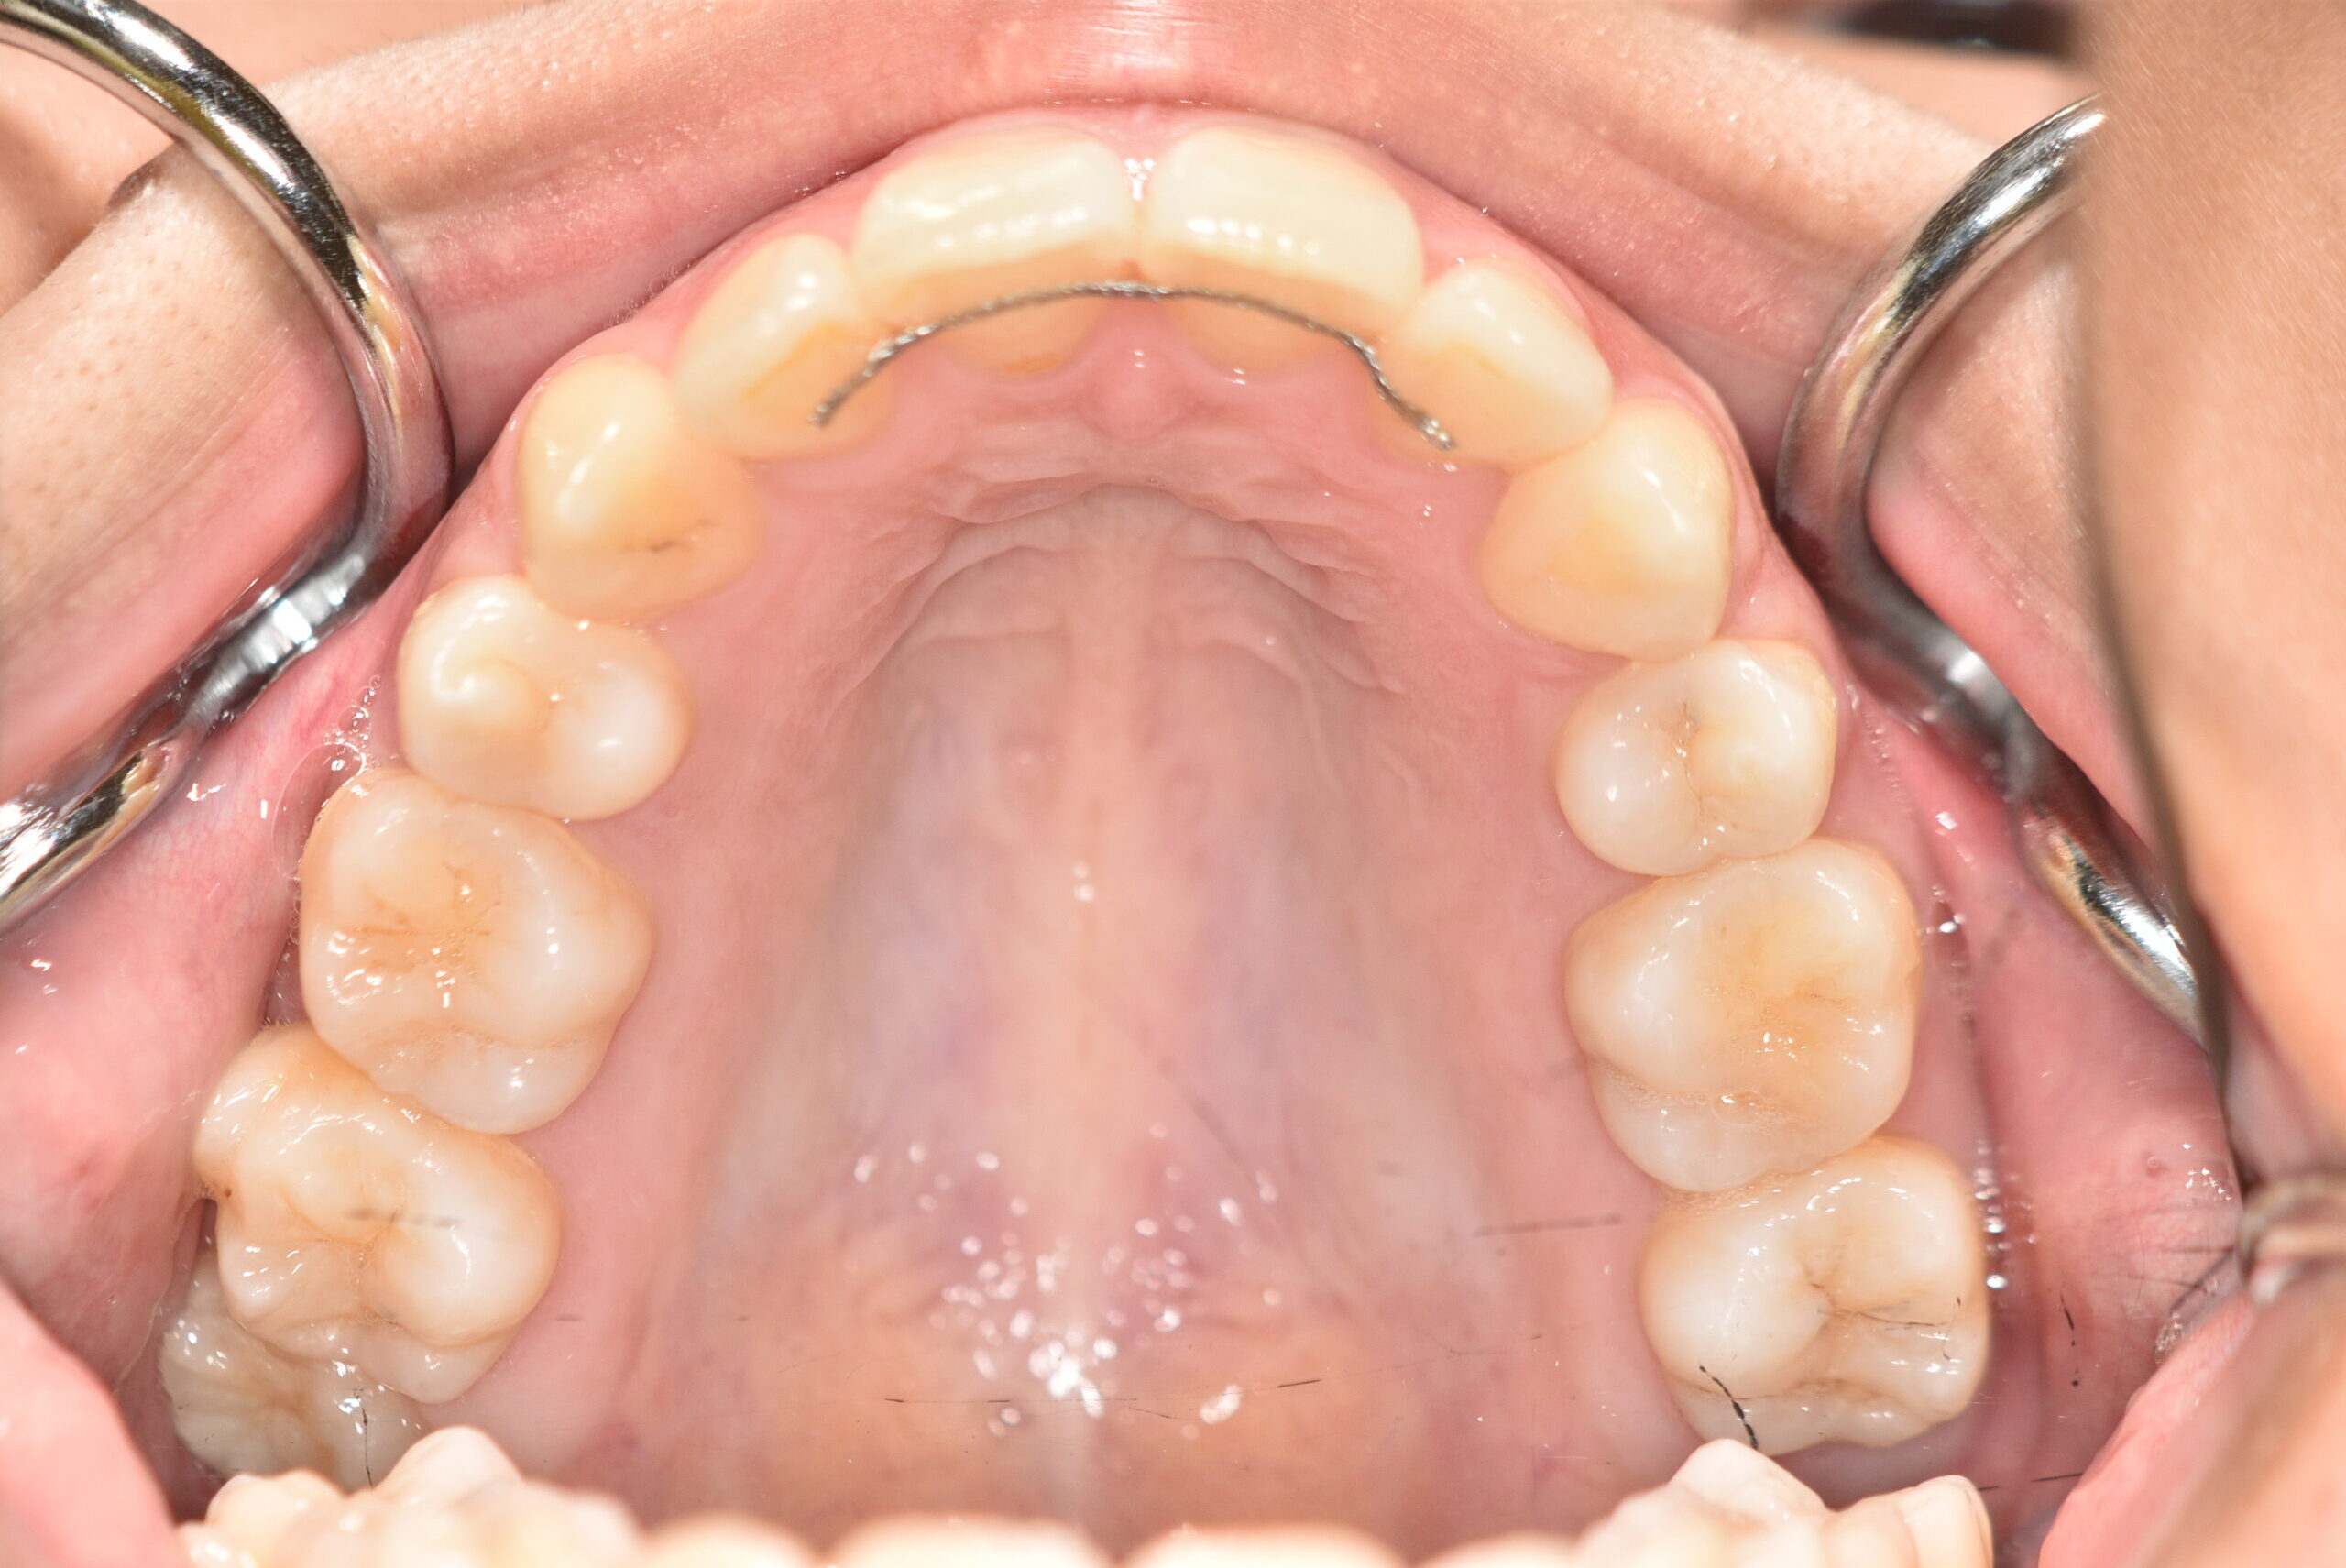

初診時

症例 症例 症例 症例

年齢

20歳5ヶ月 性 別 女性

検査の結果、上顎前突及び上下顎前歯部叢生を伴うアングルⅡ級1類不正咬合と診断しました。